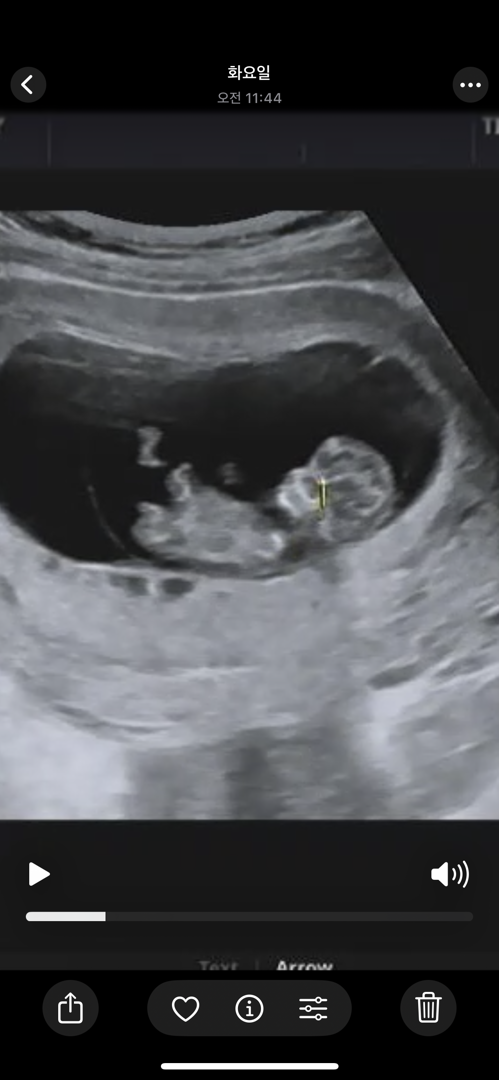

10주+5일 초음파인데 각도법 보이나요?

지피티는 딸같다는데 여러분 생각은 어떠신가요ㅎ

저게 성기라면 딸같아요!

돌기가안보여서 각도법이 어려워요

아 혹시 저기 끝에 있는게 아닌가요? 저거인줄 알았어요ㅠㅠㅠㅋ

아 흐려서 못봣네요 저거면 아마딸인거같아요